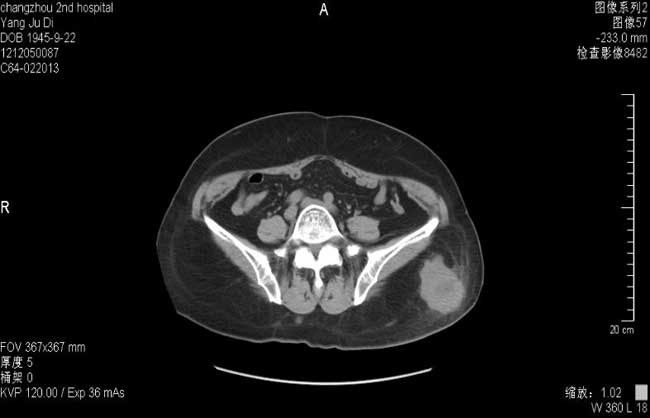

更改抗感染药物为拜复乐+SMZ+更昔洛韦,并给予氢化可的松0.1+丙种球蛋白10g*3天,经治疗患者体温正常,胸闷、气急好转,复查胸部CT肺部感染明显吸收。

2013-3-9